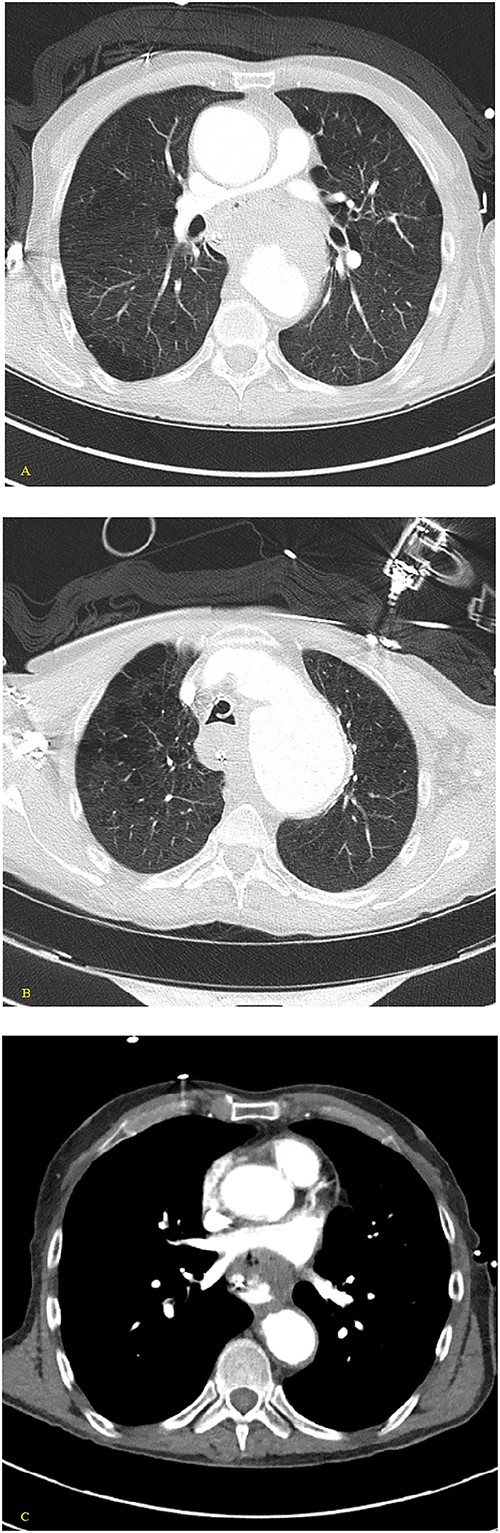

(A) Coronal and (B) sagittal views of the arterial phase CT chest with IV contrast performed during the initial trauma evaluation show aneurysmal dilation of the thoracic aorta with contrast extravasation into the esophagus and stomach.

(A–D) Coronal CT chest with contrast reveal the descending aortic aneurysm of at least 6.5-cm diameter. Deep ulceration in the descending aorta at approximately the level of the pulmonary artery bifurcation. The ulceration has eroded into the esophagus. Extravasation of contrast is observed from the ulceration into the esophagus.